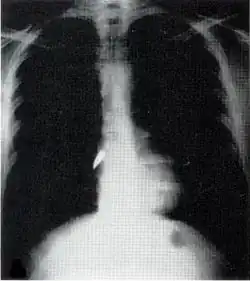

Most penetrating injuries are chest wounds and have a mortality rate (death rate) of under 10%.[14] Penetrating chest trauma can injure vital organs such as the heart and lungs and can interfere with breathing and circulation. Lung injuries that can be caused by penetrating trauma include pulmonary laceration (a cut or tear) pulmonary contusion (a bruise), hemothorax (an accumulation of blood in the chest cavity outside of the lung), pneumothorax (an accumulation of air in the chest cavity) and hemopneumothorax (accumulation of both blood and air). Sucking chest wounds and tension pneumothorax may result.

Penetrating trauma can also cause injuries to the heart and circulatory system. When the heart is punctured, it may bleed profusely into the chest cavity if the membrane around it (the pericardium) is significantly torn, or it may cause pericardial tamponade if the pericardium is not disrupted.[15] In pericardial tamponade, blood escapes from the heart but is trapped within the pericardium, so pressure builds up between the pericardium and the heart, compressing the latter and interfering with its pumping.[15] Fractures of the ribs commonly produce penetrating chest trauma when sharp bone ends pierce tissues.